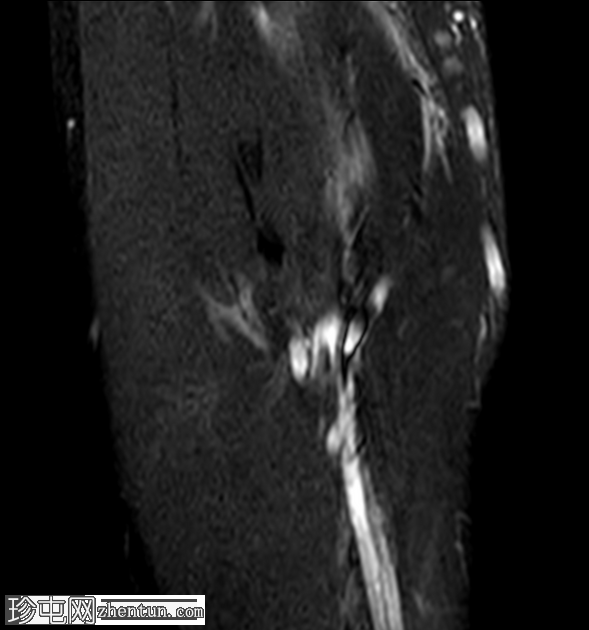

冠状位

STIR序列

尺侧副韧带显示高度撕裂,表现为模糊的异常形态,并伴有高PD信号强度。

内侧副韧带前束近端附着点显示高PD和STIR信号以及纤维断裂,符合部分撕裂的特征。

在MRI上,后外侧旋转不稳的标志性特征是尺侧副韧带(LUCL)的断裂或变薄,在冠状位T2加权或质子密度脂肪抑制序列上显示最佳。其他辅助性发现包括:伸肌总腱起点处水肿或撕裂、后外侧关节囊内有液体信号提示关节囊破裂、矢状位图像上桡骨头半脱位,以及桡骨头骨折和后外侧上髁/肱骨小头凹陷性骨折(即奥斯本-科特里尔损伤)。